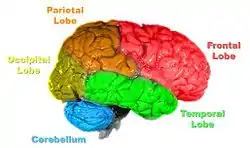

Creierul este format din trei părți principale: anterioară, medie și posterioară.

Encefalul cuprinde:

- trunchiul cerebral - aici își au originea 10 din cei 12 nervi cranieni, este sediul unor reflexe somatice și vegetative.

- cerebelul - extirparea sa generează astenie, astazie și atonie, care sunt atenuate ulterior prin compensare corticală.

- diencefalul - cuprinde talamusul, metatalamusul, subtalamusul, epitalamusul și hipotalamusul.

- emisferele cerebrale - reprezintă cea mai mare parte a sistemului nervos central.[3]